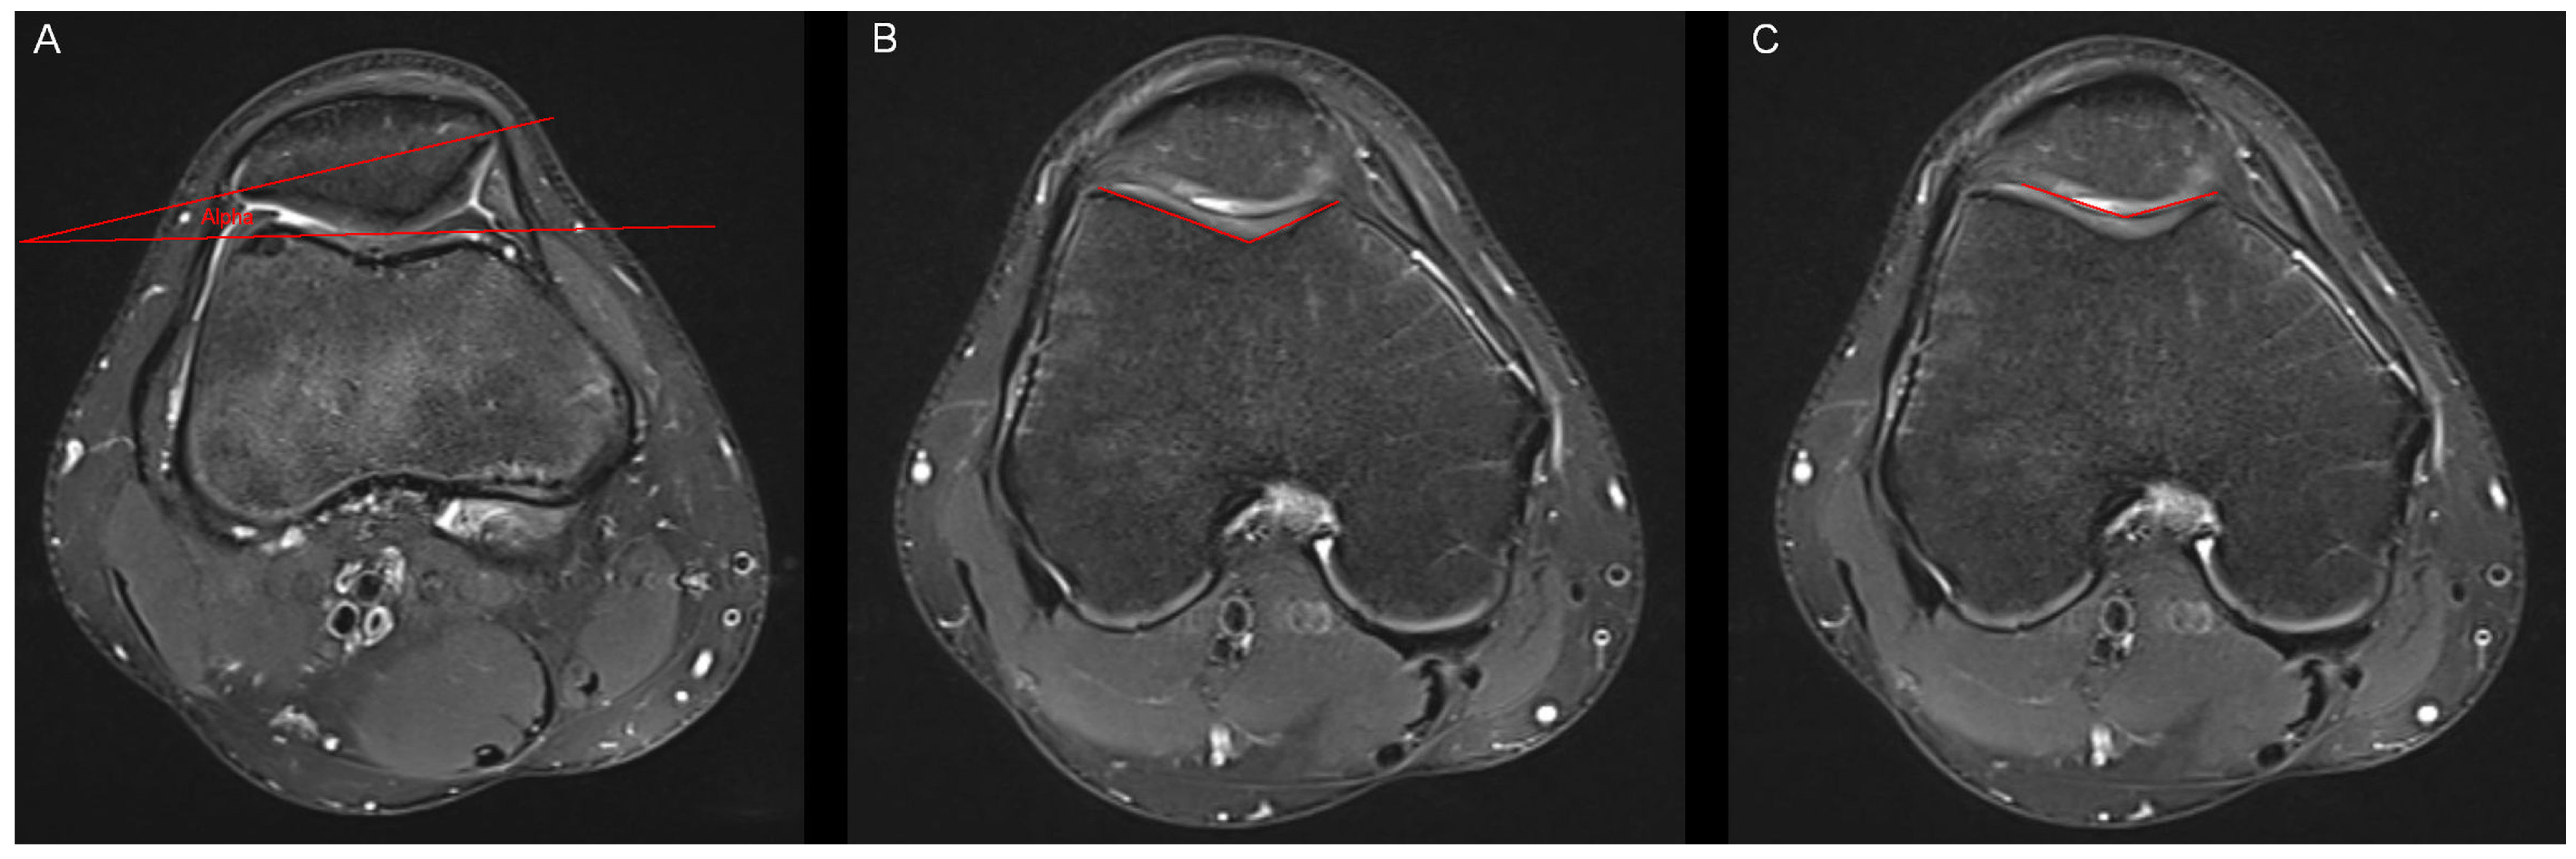

Figure 3. Measurement of the lateral trochlear inclination and the anterior tibial translocation. (A) The lateral trochlear inclination was measured through an angle (beta) between two lines. The first line was connected the posterior aspect of both femur condyles. The second line was placed on the lateral facet of the trochlea. Measurement was conducted in the axial slice offering the largest distance of the lateral facet of the trochlea. (B) The anterior tibial translocation was measured in sagittal MR-images showing the lateral femur condyle. We drew two parallel lines (line A and line B), which were also parallel to the axis of the tibia. The distance between the two lines represents the anterior tibial translocation.